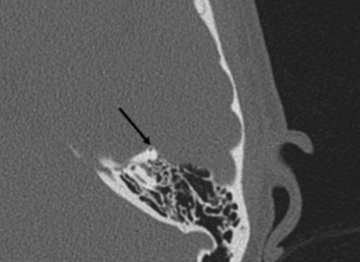

High-resolution computed tomography, which demonstates dehiscence of the left superior semicircular canal

High-resolution computed tomography (CT) scans of the temporal bone is crucial for physicians to diagnose, confirm, and locate SSCD. Sometimes CT scans can overestimate the SSCD when the size is below 3 mm. Thus, it is important to conduct other clinical and neurophysiological tests to compliment the radiological findings.